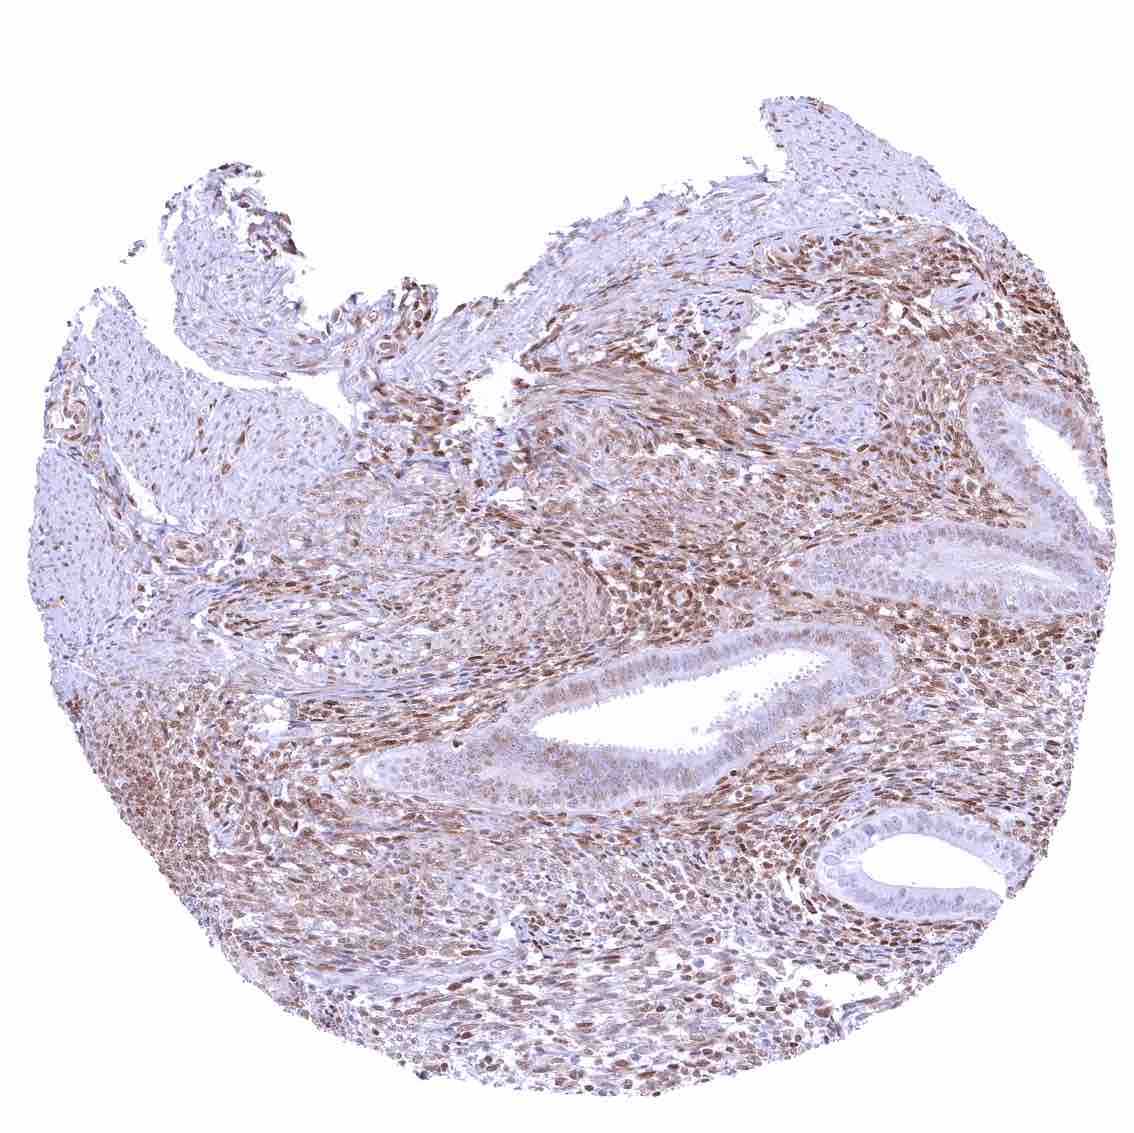

Tonsil – Strong nuclear p27 staining of a significant subset of cells, especially in the interfollicular area. Nuclear staining of squamous epithelial cells predominates in the more mature cell layers (top 50_ of the epidermis)

Tonsil, surface epithelium – Strong nuclear p27 staining of a significant subset of cells, especially in the interfollicular area. Nuclear staining of squamous epithelial cells predominates in the more mature cell layers (top 50_ of the epidermis)